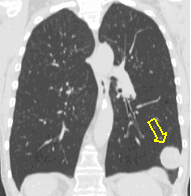

20. Miliary lung metastases. HRCT, coronal reconstruction:

60 year old man, secondary pulmonary lesions due to kidney tumor, underwent target therapy.

Lobulated nodule in the left lung, associated with the pleura dorsobasally.

Lobectomy because of right lung adenocarcinoma, (brain metastasis). (by the contribution of Zsuzsanna Monostori, MD, PhD)